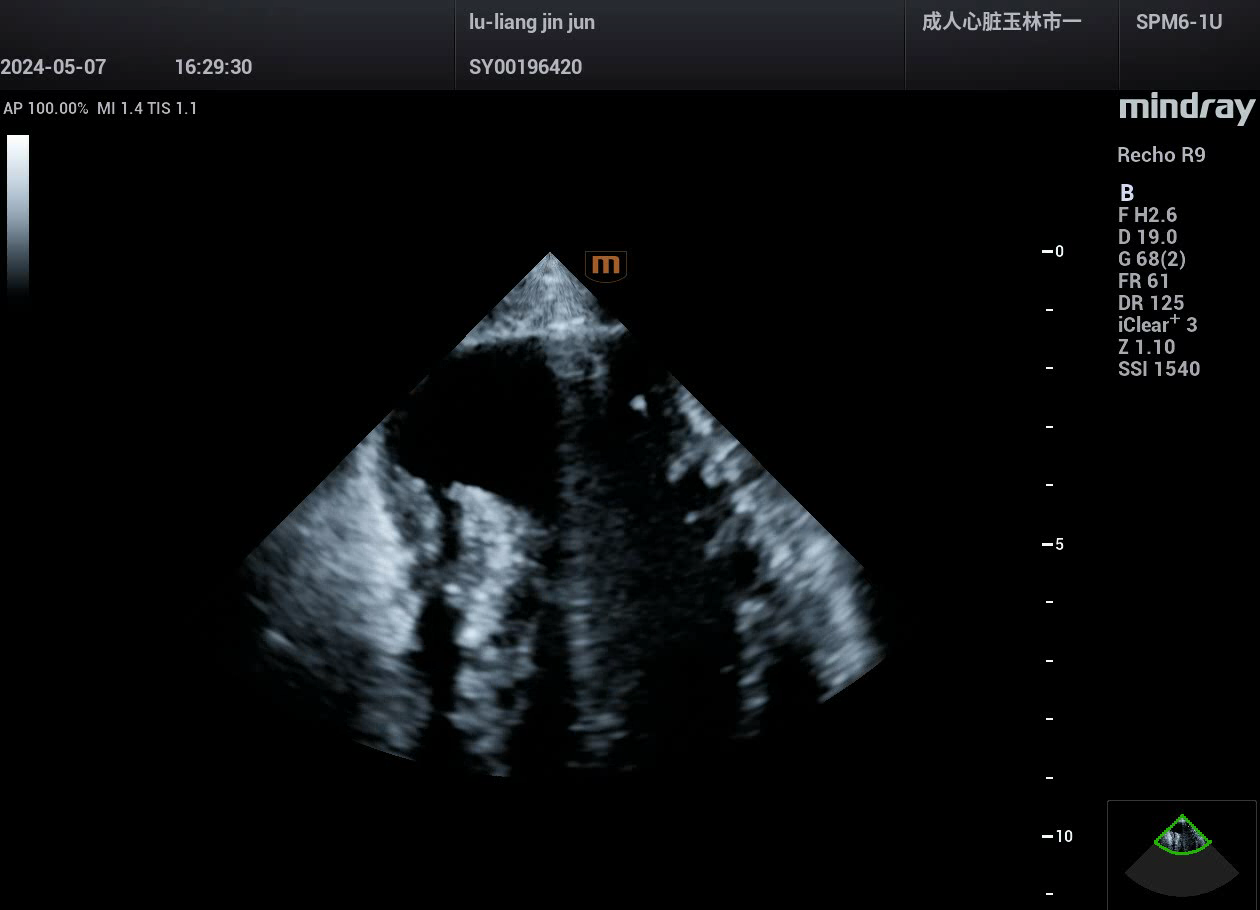

病例,急性心肌梗死,并发室间隔穿孔,迈瑞心脏彩超鲲鹏Recho R9,2024年5月

病例,急性心肌梗死,并发室间隔穿孔。

病例来源,玉林市第一人民医院超声科。

迈瑞心脏彩超鲲鹏Recho R9,2024年5月。